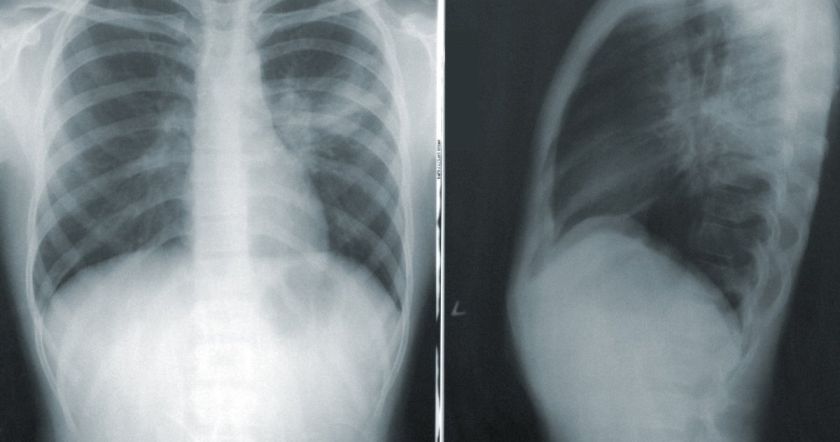

Большинство случаев обструкция верхней полой вены вызваны раком легкого. Он может распространиться на близлежащие лимфатические узлы (железы), которые становятся опухшими.

Рак легких является распространенной и серьезной формой рака. Обнаружение тонких изменений имеет решающее значение, поскольку рак легкого на ранней стадии часто не имеет заметных признаков.